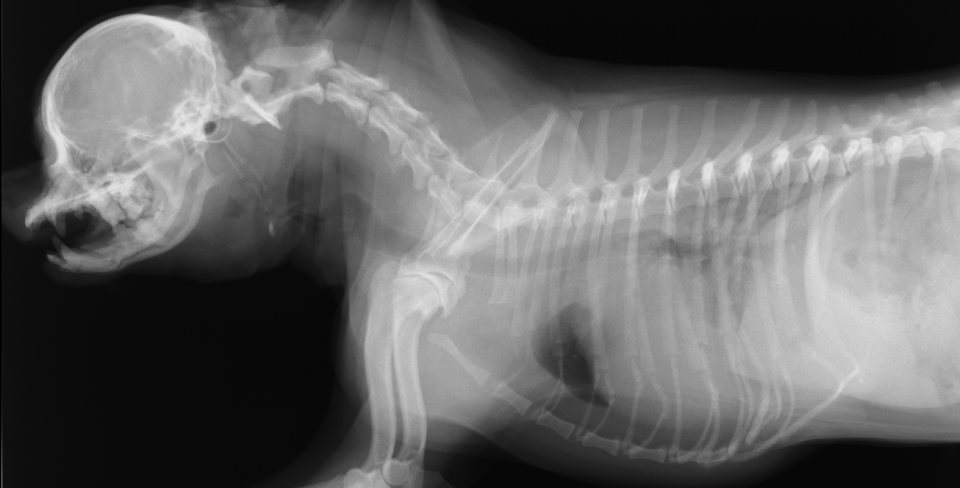

わんちゃんの巨大食道症。食道炎から二次的に起きる場合や、重症筋無力症の症状として発症する場合があります。合併症の誤嚥性肺炎の危険性があり、食後の立位の維持や少量ずつの食事などの看護が必要です。

重度な巨大食道と誤嚥性肺炎のわんちゃん

わんちゃんの巨大食道症。食道炎から二次的に起きる場合や、重症筋無力症の症状として発症する場合があります。合併症の誤嚥性肺炎の危険性があり、食後の立位の維持や少量ずつの食事などの看護が必要です。

重度な巨大食道と誤嚥性肺炎のわんちゃん